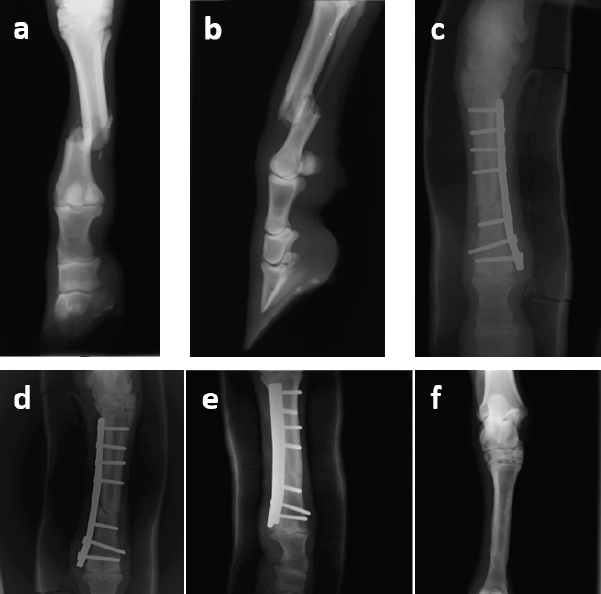

A deep puncture wound on the right hind limb at the medial aspect of the canon was detected. Moderated soft tissue swelling and blood were detected. Exploration of the wound revealed a movable bone fragment protruding through the wound and after performing radiographs this was confirmed to be part of the third metatarsus, thus this fracture could be classified has type II – open fracture with large skin laceration but little actual tissue loss (Nixon, 1996). Radiographic examination confirmed that the presented fracture was a simple complete diaphyseal fracture with slight obliquity of the right Mt3 (Fig. 1a and b).

After discussion about prognosis with the owner, surgical repair was opted. The anaesthetic protocol was performed through premedication with detomidine (Domidine™, Dechra, United Kingdom; 0.01 mg/kg IV), acepromazine (Calmivet™, Vetoquinol, Portugal; 0.04 mg/kg IV) and butorphanol (Butomidor™, Richter Pharma, Austria; 0.04 mg/kg IV) and, after 10 minutes, anesthesia was induced with ketamine (Ketamidor™, Richter Pharma, Austria; 2.0 mg/kg IV) and diazepam (Diazepam, Labesfal, Portugal; 0.1 mg/kg IV). After placement of the endotracheal tube, the anesthesia was maintained through isoflurane (IsoVet®, BBraun, Germany; 1.3%) in oxygen (rebreathing circular circuit system) for 3 hours (Tafonius Wind God—Hallowell EMC model, Vetronic Services Ltd, Devon, UK). The animal was placed in left lateral recumbency with the lateral aspect of the right hindlimb uppermost for a dorsolateral approach to Mt3 for plate application. A curvilinear skin incision was performed from the tarsometatarsal joint to the tarsophalangeal joint and the long digital extensor tendon and overlying fascia were retracted (Schneider and Sampson, 2020). The application of a single 8-hole 4.5 mm broad DCP in compression function, fixed with seven cortical screws (4.5 mm), was carried out to stabilize the fracture (with four screws in the proximal fragment and three in the distal one) in the Mt3 lateral bone surface (Fig. 1c). During the surgical procedure the surgeon opted to do not place a lag compressive screw through the fracture line since the obliquity of the same was very slight. The incision was routinely closed in two layers, and an adhesive elastic pressure bandage was applied.

Post-operative antimicrobial treatments with penicillin associated to dihydrostreptomycin (Pendistrept™, Syva, Spain; 25,000 UI/kg and 31.25 mg/kg IM, respectively) and enrofloxacin (Baytril 10%, Bayer, Germany; 5.5 mg/kg IV) were administered for 15 days. Post-operative analgesia was mainly provided by phenylbutazone (Phenylarthrite Inj., Vetóquinol, Portugal; 4.4 mg/kg IV). Additional external coaptation with full limb cast composed internally by orthopedic padding and externally with veterinary casting tape (Vetcast Plus®), was maintained postoperatively during 1 month for additional movement limitation (Fig. 2). This cast was cut with an oscillating saw and taken off to revaluation of the surgical wound 15 days after surgery and a new cast was then applied again as described. Postoperative radiographic evaluation (dorsopalmar and lateromedial views) was performed in a biweekly period during the first post-surgery month and thereafter radiographs were taken monthly (Fig. 1d and e). The animal stayed for a 3 months period at a hospital stall with 1.5 meters width by 2.5 meters length. At this moment, due to a slight lameness and swelling of the metatarsophalangeal joint and since bone repair was proven by radiographic monitoring (Fig. 1f), it was decided to remove the internal implants, having the pony fully recovered after this procedure (Fig. 3).

Fig. 1. Radiographic images of the third right metatarsus: (a) and (b) in dorsopalmar and lateromedial views in the preoperative period, and dorsopalmar views in the (c) immediate postoperative period, (d) fourth postoperative week, (e) second postoperative month and (f) third month after surgery and after the removal of the implants.